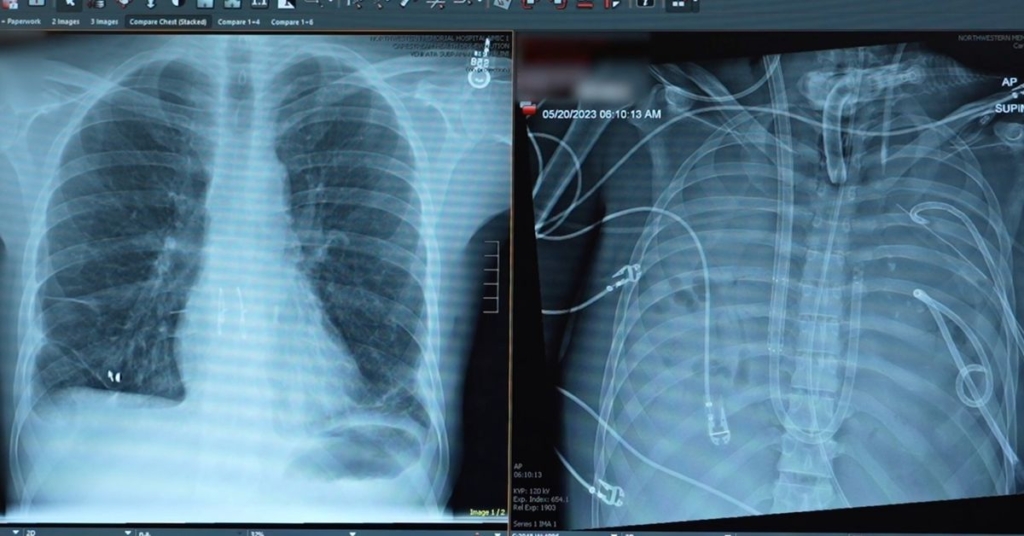

ABD’deki cerrahlar, göğsünde akciğer olmadan 48 saat boyunca bir adamı hayatta tutmayı başardı ve ardından başarılı bir nakil gerçekleştirdi. Northwestern Üniversitesi’ndeki doktorlar, hastanın enfekte olan akciğerlerini çıkararak, ona bir yapay akciğer seti kurdular ve böylece nakil için beklerken hayatta kalmasını sağladılar.

Yapılan incelemeler sonucunda, hastanın akciğerlerinin tamir edilemeyecek kadar hasar gördüğü ve çift akciğer nakli dışında bir kurtuluş yolu bulunmadığı belirlendi. Ancak hastanın durumu, hemen yeni akciğerleri kabul edecek kadar iyi değildi.

Ekip, hastanın akciğer işlevlerini geçici olarak yerine getiren bir yapay akciğer sistemi geliştirdi. Bu sistem, kanı oksijenlendiriyor, karbondioksiti temizliyor ve kalp ile vücut arasında stabil bir kan akışı sağlıyordu.

Akciğerler çıkarıldıktan sonra hastanın durumu hızla düzelmeye başladı. Kan basıncı stabil hale geldi, organ fonksiyonları geri kazandı ve enfeksiyon azaldı. İki gün içinde, uygun donor akciğerler bulundu ve cerrahlar çift akciğer nakli gerçekleştirdi.